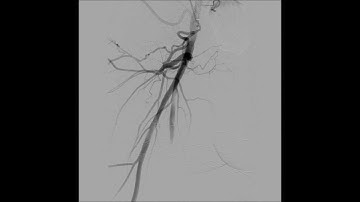

TruePath Popliteal CTO